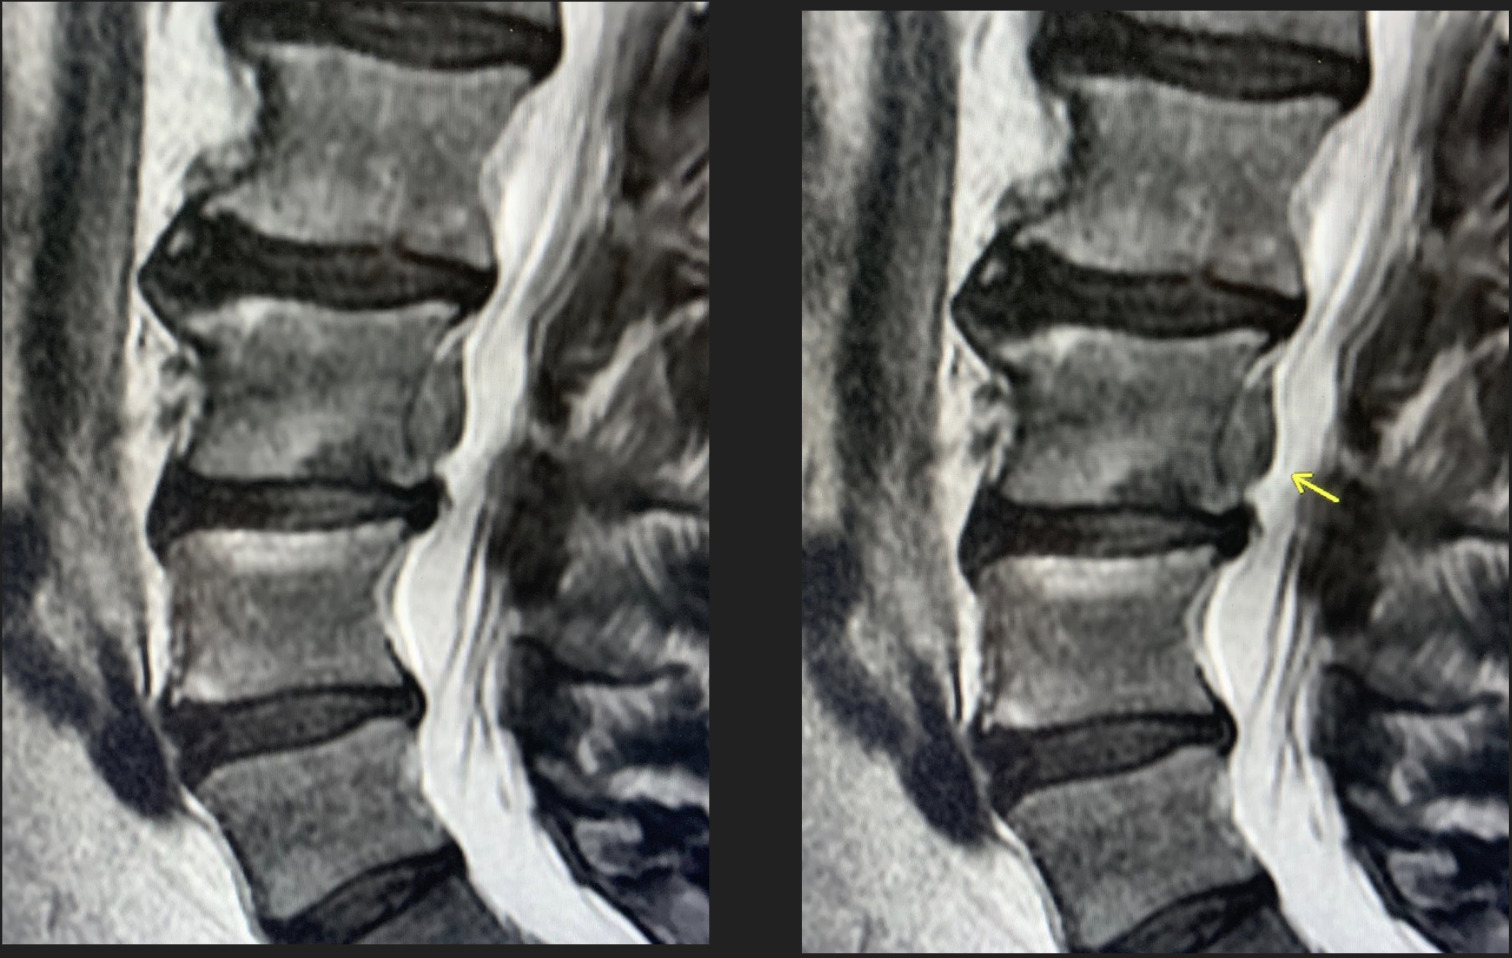

Imaging was performed with an MRI of the lumbar spine with and without contrast. The MRI (Figures 1-3) demonstrated a large L3 vertebral body inferior endplate Schmorl’s node with posterior extension through the vertebral body cortex. This Schmorl’s node extended into the ventral epidural space superiorly with severe effacement of the suitable L2-L3 subarticular recess, as well as the right L3-L4 neural foramen, impinging on the proper L3 nerve root. Additionally, there was surrounding cortical edema and enhancement, suggesting an acute Schmorl’s node.

_and_stir_(right)_images_demonstrating_a_schmorl_s_node_with_disc_materi.png)